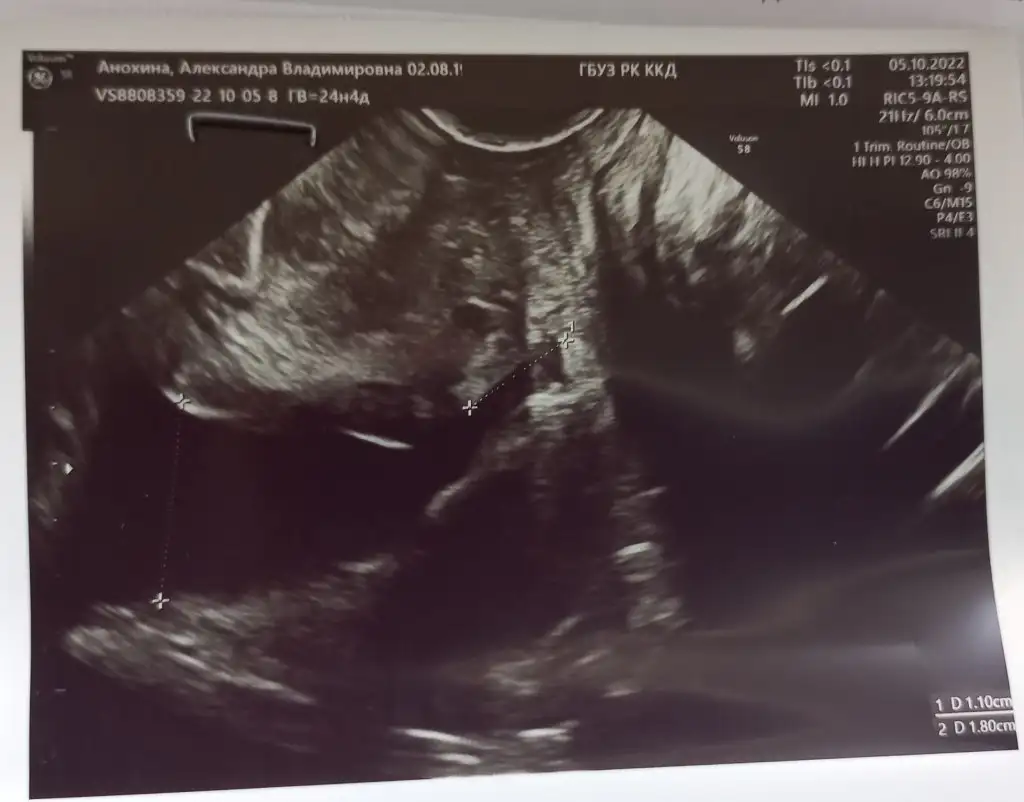

Bu geçen haftadaki ultrason. Solda çocuğun başı sonra iç acilma ve sonra kısa rahim ağzı. Rahim agzi hiç kalmamış ve iç acilma devam ediyor